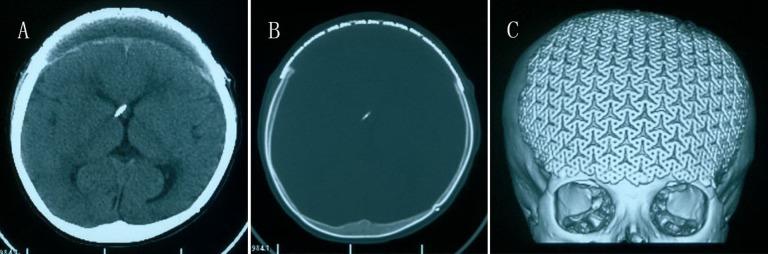

Hyperostosis frontalis interna is an unexplained irregular thickening of the inner table of the frontal bone. Hyperostosis frontalis interna was first identified in 1719 by Morgagni as a symptom of a more generalized syndrome characterized by virilism and obesity. Most current studies have shown hyperostosis frontalis interna to be a sex- and age-dependent phenomenon, and females manifest a significantly higher prevalence of hyperostosis frontalis interna than males. In this article, the authors report the clinical case of hyperostosis frontalis interna in a 7-year-old child who had severe traumatic brain injury in the past; review the related literature; and discuss the clinical, radiological, and therapeutic features of this condition.

额骨内板增生症是一种原因不明的额骨内板不规则增厚。额骨内板增生症于1719年由莫尔加尼首次发现,是一种以男性化和肥胖为特征的更广泛综合征的症状。目前大多数研究表明,额骨内板增生症是一种与性别和年龄相关的现象,女性额骨内板增生症的患病率明显高于男性。在本文中,作者报告了一名曾有严重创伤性脑损伤的7岁儿童患额骨内板增生症的临床病例;回顾相关文献;并讨论该病症的临床、放射学和治疗特征。